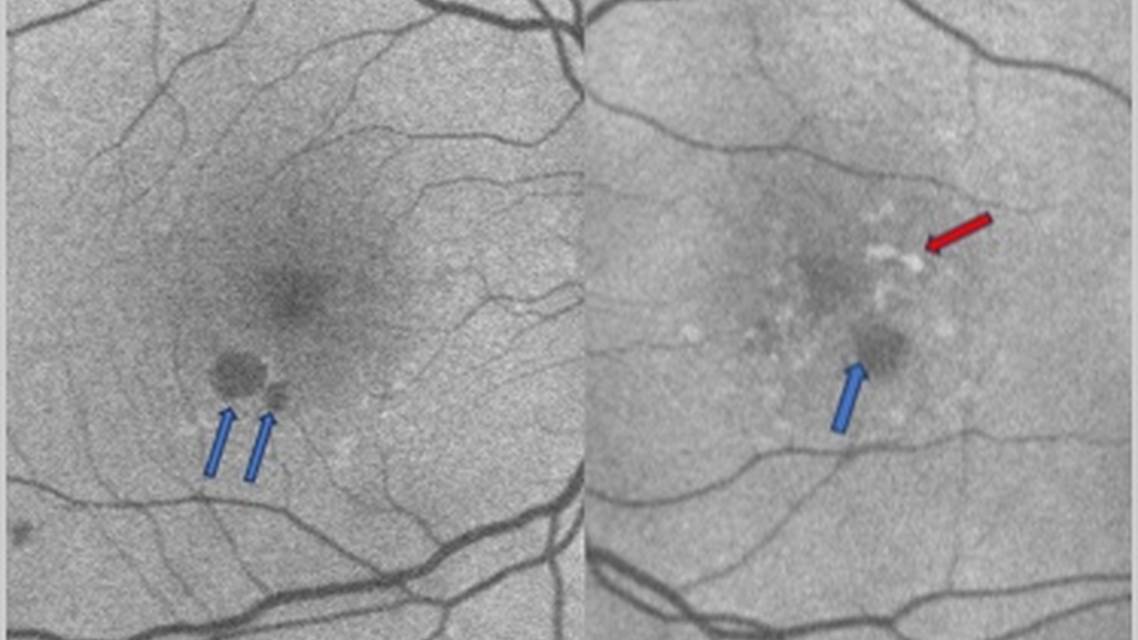

A 72-year-old white man was referred by his local optometrist for an evaluation of age-related macular degeneration (AMD) in the right and left eyes. The patient reported having difficulties reading small print and said he thinks he is seeing distortion in the left eye, which he described as wavy lines. The patient denied flashes, floaters, pain, or redness in either eye. Relevant medical history included diagnoses of systemic hypertension, arthritis, and thyroid disease. Family medical history was positive for macular degeneration (mother and father), stroke (father), and thyroid disease (mother). As for past ocular history, the patient’s status was post phacoemulsification with PCIOL implantation OU 2 years prior, and there was a history of posterior vitreous detachment OU. Presenting VA was 20/20 J1 OD and 20/20 J2 OS. Imaging captured at this initial visit, in March 2022, confirmed a diagnosis of geographic atrophy (GA) with hyperautofluorescence OS (Figures 1 and 2).

The patient was instructed to continue taking AREDS2 vitamins. In addition, the patient was educated on the need to monitor vision with an Amsler Grid and to call the office with any new distortion or changes. The patient subsequently returned to his primary care optometrist for a dilated fundus examination and routine care. One year and 4 months later the patient returned to our clinic with worsening distortion and vision changes in both eyes (OS>OD). The patient relayed that he wanted to learn more about the new treatments available for AMD that his primary care optometrist informed him of. VA at the time of this visit, in July 2023, was 20/20 J3 OD and 20/300 at distance and 20/400 at near OS. Imaging captured at this follow-up visit confirmed worsening of the GA OU (Figures 3 and 4). Unfortunately, the patient’s insurance was not covering GA treatment at this time, and so he was instructed to follow up in 6 months with hopes that his insurance would be able to cover treatment.

A second notable feature of this case is the difference in progression between the two eyes. Although GA was evident in each eye at the initial visit (Figures 1 and 2), the presence of hyperautofluorescence in the left eye suggested a worse prognosis. Indeed, over the course of this patient’s journey, serial imaging was useful for confirming progression of the lesions in each eye.